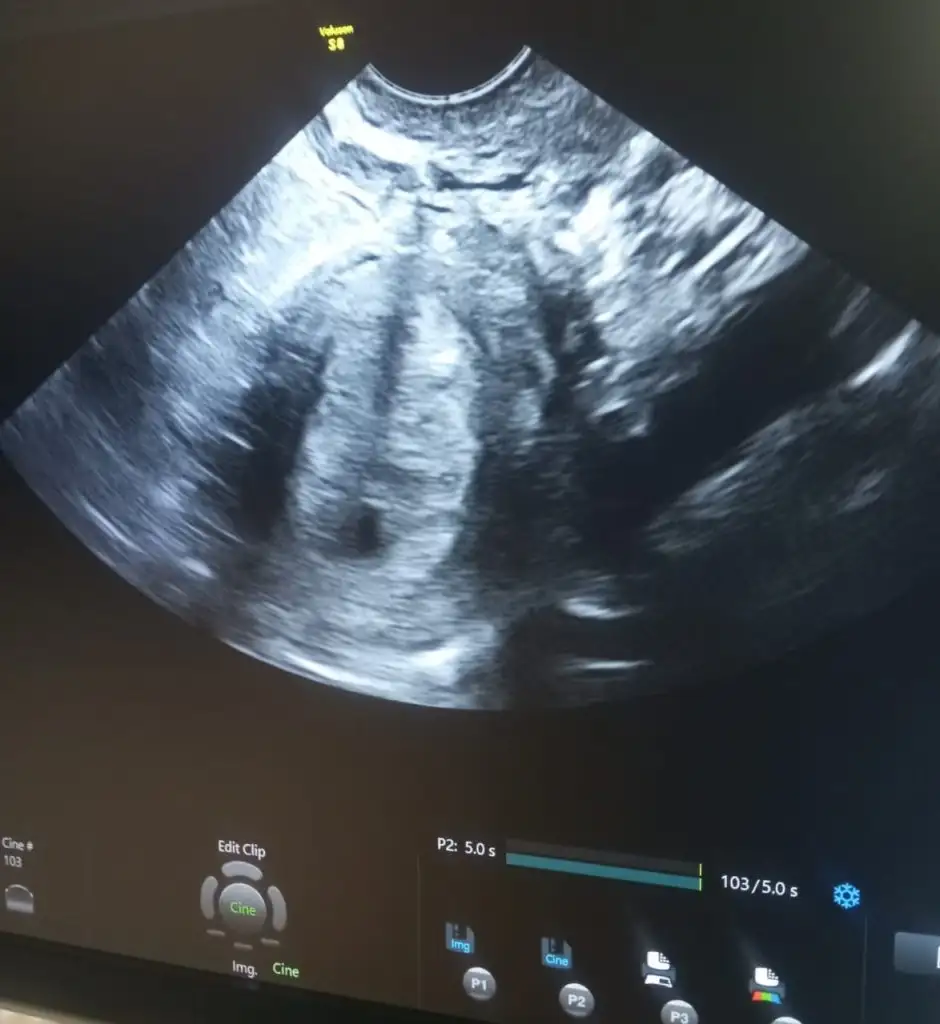

Selam canım evet 21 Aralık tı ben pazartesi günü gittim kontrole keseyi gördüm çok şükür ❤️ 2-3 hafta sonra kontrole gel dedi kalp atışı için gideceğim.. Ayy sen kalp atışını da duyarsın, o zaman gittiğinde inşallah 🐣🐣

Merhaba allah tamamına erdirsin🙏 kese görüntünüz var mı acaba